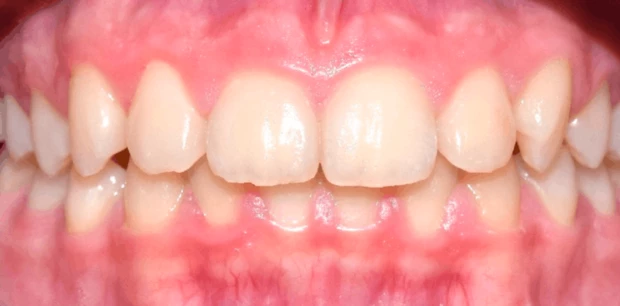

Профгигиена

Профессиональная гигиена полости рта

Выполнено удаление зубного налёта и камня: восстановлен естественный цвет эмали, улучшено состояние дёсен и профилактика воспалений.